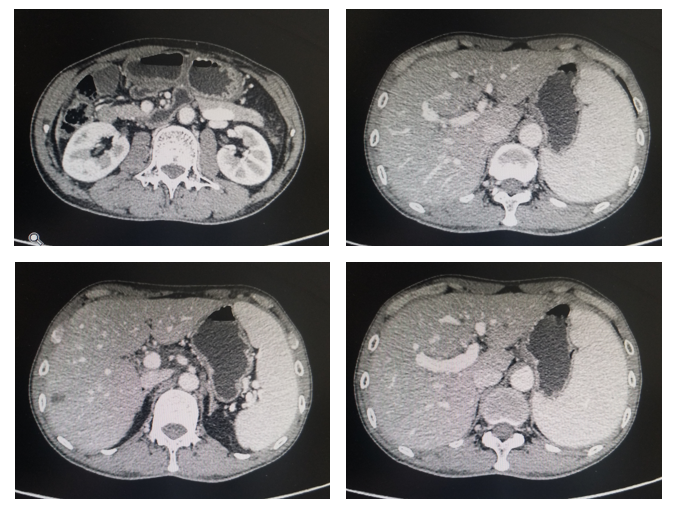

上腹CT:肝内多发低密度结节,胃窦区胃壁增厚(图1)。

影像科:从CT看,该患者胃窦区胃壁增厚,肝内多发结节,结合胃镜及病理结果,考虑原发性胃癌诊断明确,肝脏病灶为转移性病灶,因此,考虑胃癌晚期伴多发肝转移诊断成立。